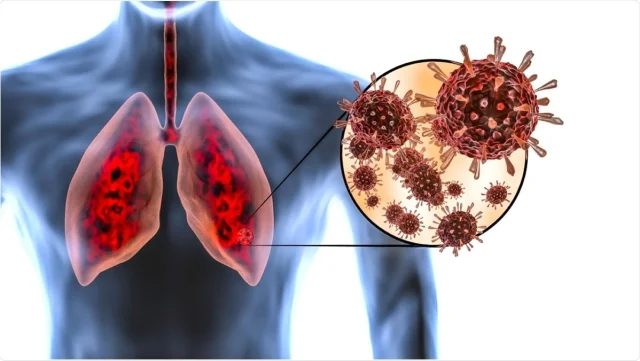

আবারও চিনে নতুন এক ভাইরাসের প্রকোপ দেখা দিয়েছে। এইবার সংক্রমণের কেন্দ্রবিন্দু হিউম্যান মেটানিউমোভাইরাস (এইচএমপিভি)। চিন থেকে শুরু হয়ে ভাইরাসটি এখন আশপাশের দেশগুলোতেও দ্রুত ছড়িয়ে পড়ছে, যা মানুষের মধ্যে নতুন করে উদ্বেগ তৈরি করেছে। বিশেষজ্ঞদের মতে, এটি আপাতত শুধুমাত্র শীতকালীন সংক্রমণ হিসেবে চিহ্নিত হয়েছে।

এইচএমপিভি বা হিউম্যান মেটানিউমোভাইরাস কী?

২০০১ সালে প্রথম শনাক্ত হওয়া এইচএমপিভি একটি শ্বাসতন্ত্রজনিত ভাইরাস, যার প্রভাব প্রধানত বাচ্চা, প্রবীণ এবং রোগ প্রতিরোধ ক্ষমতা কম এমন সব ব্যক্তিদের উপর পড়ছে। এটি প্যারামিক্সোভাইরিডি পরিবারভুক্ত ভাইরাস এবং রেসপিরেটরি সিনসাইটিয়াল ভাইরাসের (আরএসভি) আর একটি রূপ। ভাইরাসটি প্রধানত হাঁচি-কাশির মাধ্যমে ছড়াচ্ছে। শীতের শেষে বা বসন্তকালে এর প্রকোপ বেশি দেখা যায়, যদিও এটি বছরের যে কোনও সময় সংক্রমিত হতে পারে।

– গলা ব্যথা। তবে এটি গুরুতর ক্ষেত্রে নিউমোনিয়া বা ব্রঙ্কিওলাইটিসের মতো রোগের সৃষ্টি করতে পারে।

এইচএমপিভি-র ইনকিউবেশন পিরিয়ড ৩-৫ দিন। জটিল উপসর্গ দেখা দিলে নিউমোনিয়া পরীক্ষা করানো জরুরি।